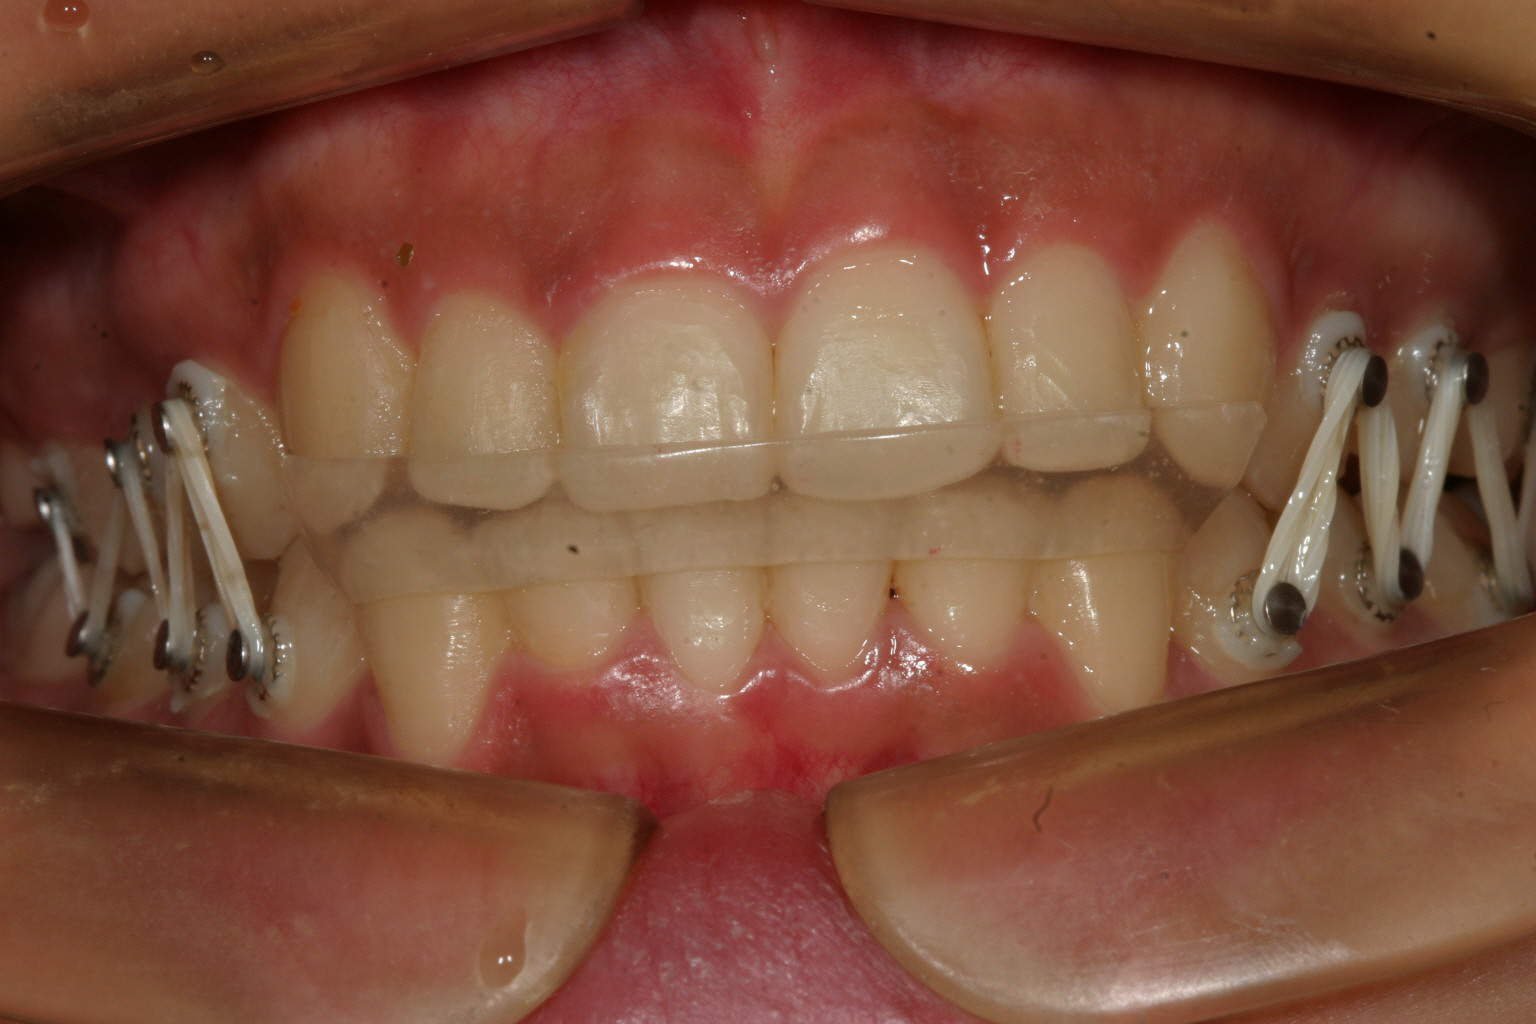

かみあわせが深い為下の前歯が見えない。

上の前歯が中に入っている為、下あごが前に出ずらく顎関節症をおこし易い咬み合わせです。

上の前歯に押されたせいで下の前歯がガタガタになっています。

かなりのオーバーバイトです。

綺麗なオーバーバイトに改善しました。